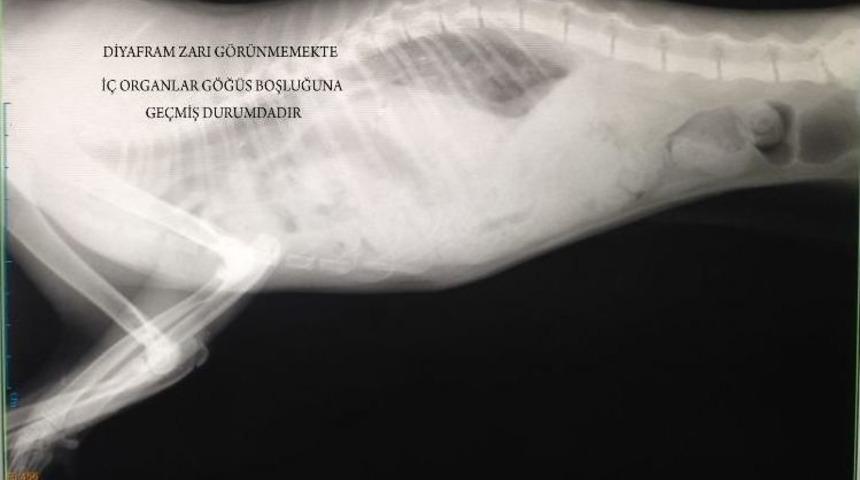

Fıtığı yırtıldığı için nefes alıp vermekte güçlük çeken 10 aylık kedi, Erciyes Üniversitesi (ERÜ) Veteriner Fakültesi Eğitim Araştırma ve Uygulama Hastanesinde yapılan ameliyatla sağlığına kavuştu.10 aylık kedi, hasta sahibi tarafından solunum problemi ve yetersizliği olduğu gerekçesi ile ERÜ Veteriner Fakültesi Eğitim Araştırma ve Uygulama Hastanesine getirildi. Daha önce antibiyotik tedavisi uygulanan ancak hastalığına çare bulunamayan kedi, burada eski sağlıklı günlerine geri döndü.Yaklaşık 2 saat süren ameliyatla ilgili bilgi veren ERÜ Veteriner Fakültesi Cerrahi Anabilim Dalı Öğretim Üyesi Prof. Dr. Gültekin Alan, “Yaptığımız klinik incelemede hastanın karın solunumu yaptığı, soluk alışverişinde ciddi bir güçlük olduğunu gözlemledik. İleri tetkik amacıyla yaptığımız röntgen bulgularında da, karın organlarının göğüs boşluğu içinde olduğunu tespit ettik ve acilen hastanın operasyonuna karar verdik. Aynı gün yaptığımız operasyonda, ki bu kompleks bir operasyondu, yırtılan diyafram bölgesi dikildi ve hastanın tekrar eski sağlığına kavuşması sağlanmış oldu” diye konuştu.